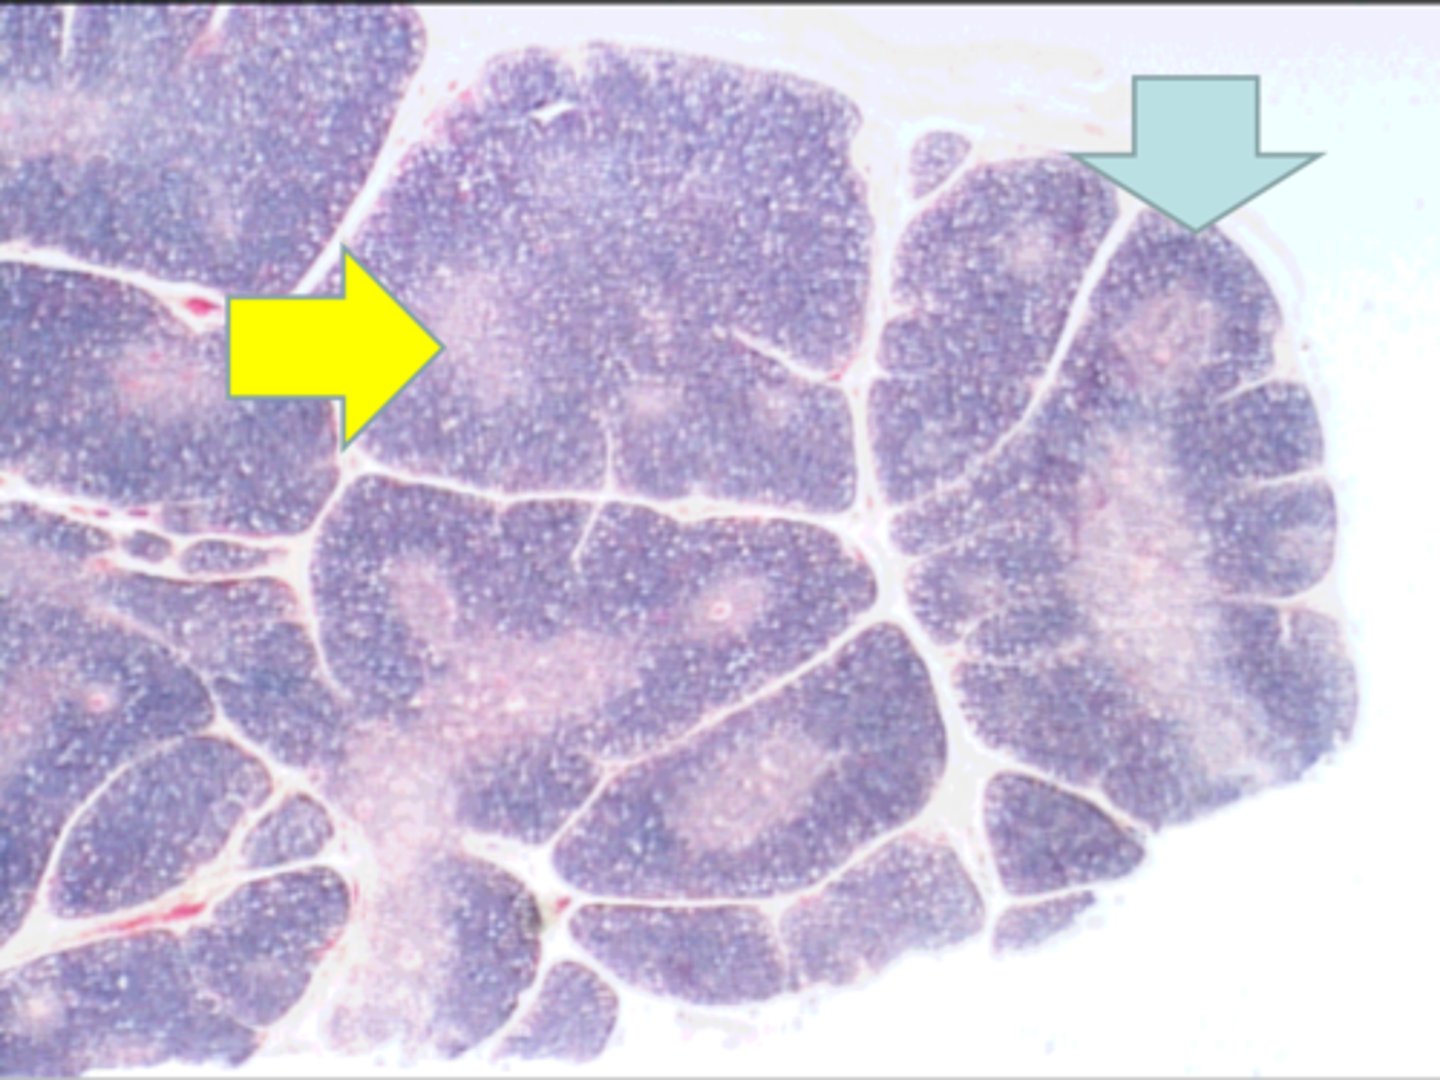

thymus

where is this tissue? thymus

yellow arrow

medulla containing T lymphocytes

blue arrow medulla containing T lymphocytes

Hassall's corpuscle

red arrow Hassall's corpuscle

Where is this tissue located? thymus

Thymus - Hassall´s corpuscle

blue arrow Thymus - Hassall´s corpuscle